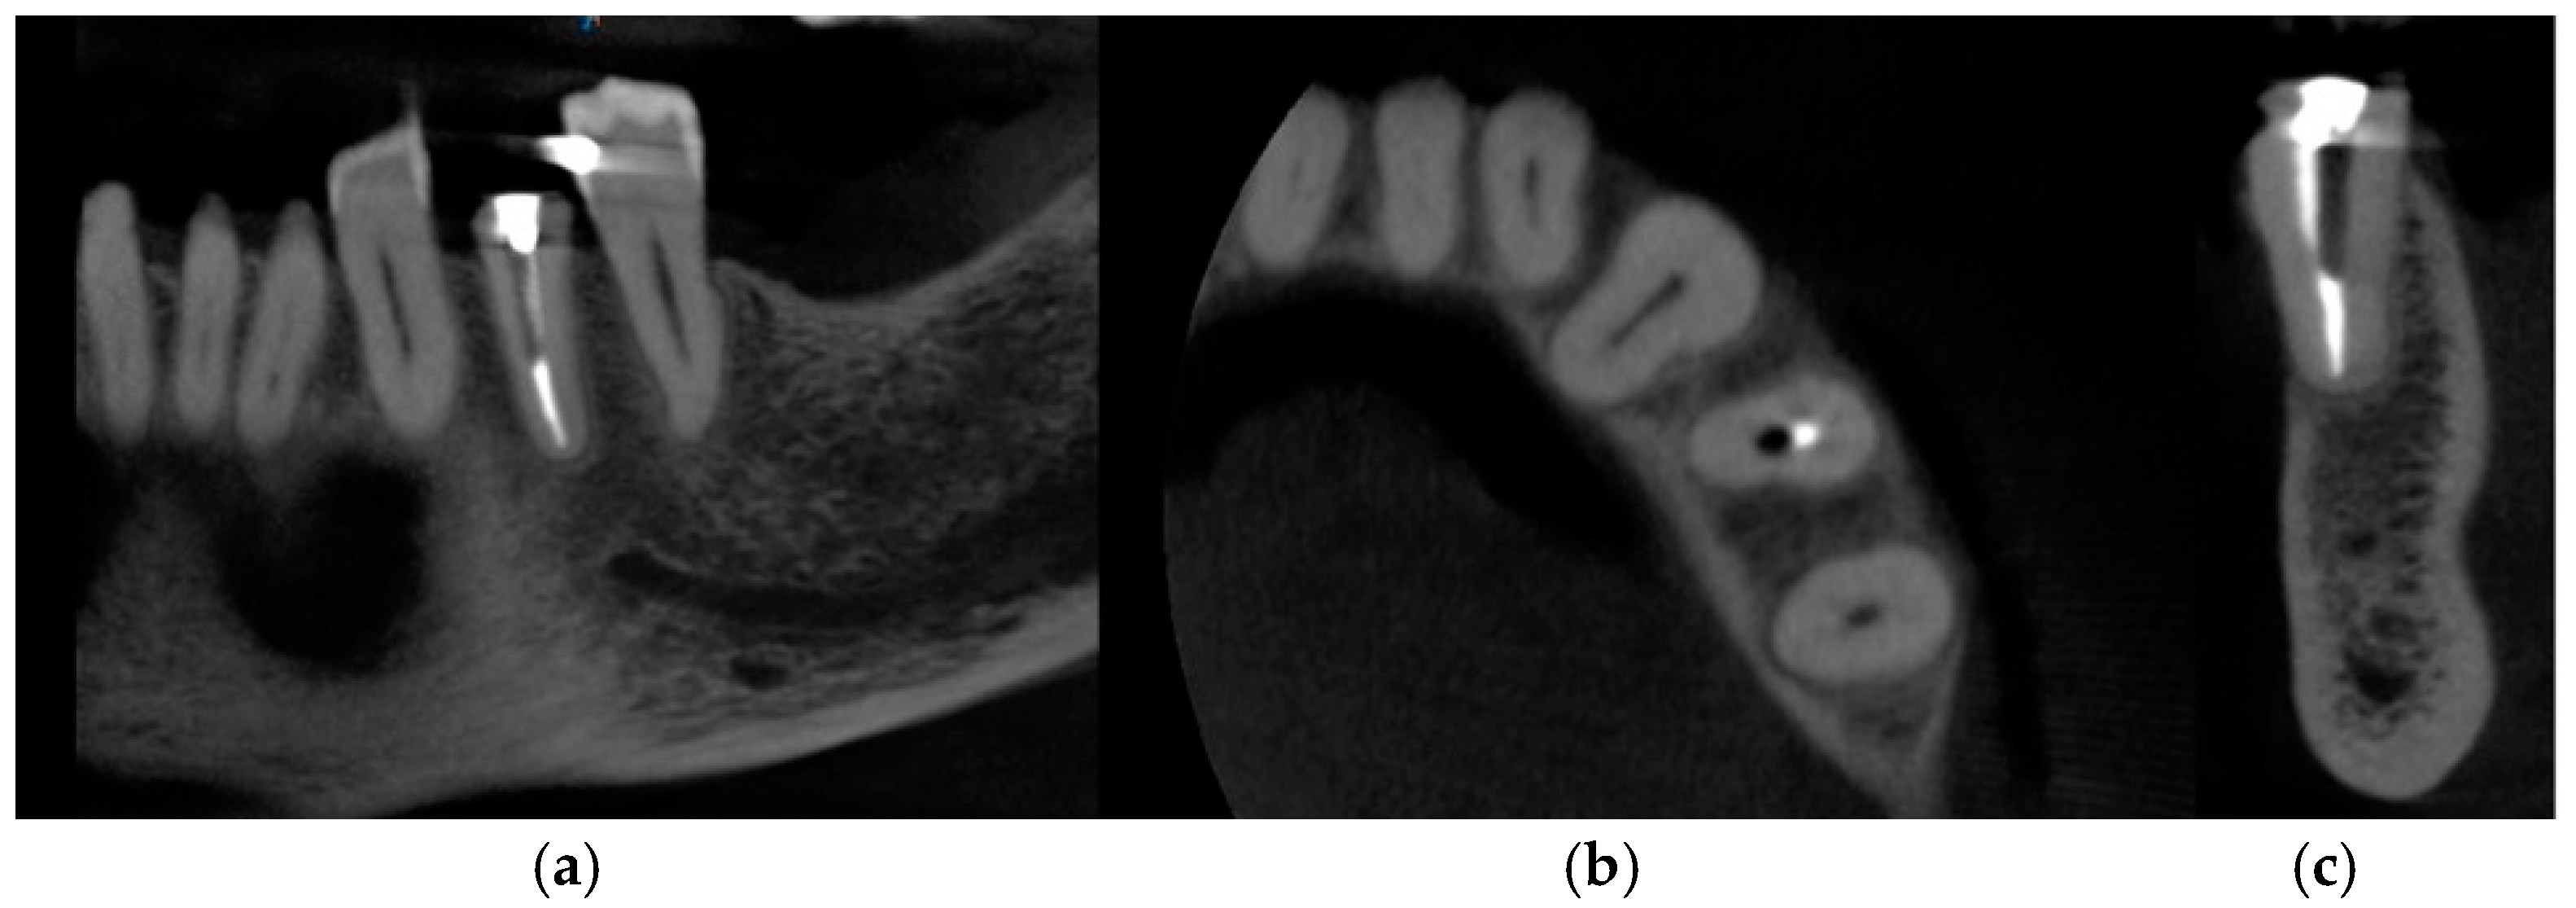

The following case study report was performed in the private clinic Dott. A Grassi, in compliance with the patient who satisfied the inclusion criteria and was included in the present study: male, 62 years old, not a smoker, and in general good health. Written informed consent was signed by the patient for the clinical procedure and for the present study. The patient was provided with a prophylaxis starting the day before the surgery for 6 days, with 2 g of amoxicillin and clavulanic acid. Pre-operative CBCT with a Carestream 8100 3D (Carestream Dental, Atlanta, GA, USA) was performed (Figure 1a–c).

Figure 1. CBCT images of the patient before the surgery: (a) frontal section, (b) transversal section, and (c) sagittal section.